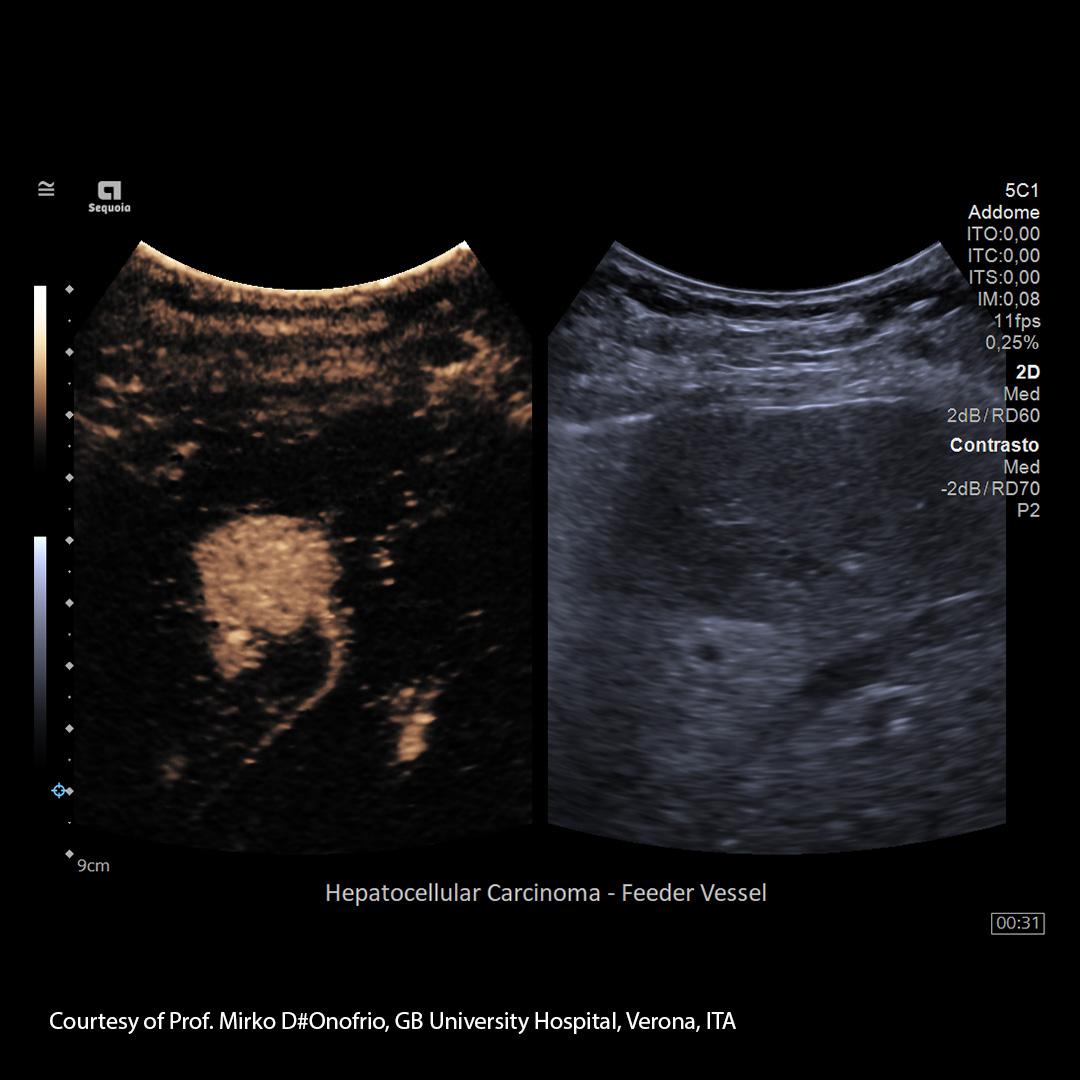

By contrast, diagnosing liver cancer requires a physical examination and special medical tests. Diagnosis of hepatocellular carcinoma (HCC) is done using imaging tools like ultrasound, computed tomography (CT), or magnetic resonance imaging (MRI) and in many cases doesn’t even require biopsy.

Embolization combines the effects of regional chemotherapy with those of ischemic necrosis induced by arterial embolization. It takes advantage of the fact that the perfusion of hepatocellular carcinomas (HCC) and liver metastases from other types of cancer is mostly through hepatic arteries, allowing interventional radiologists to selectively deliver anti-tumor substances through the arteries.